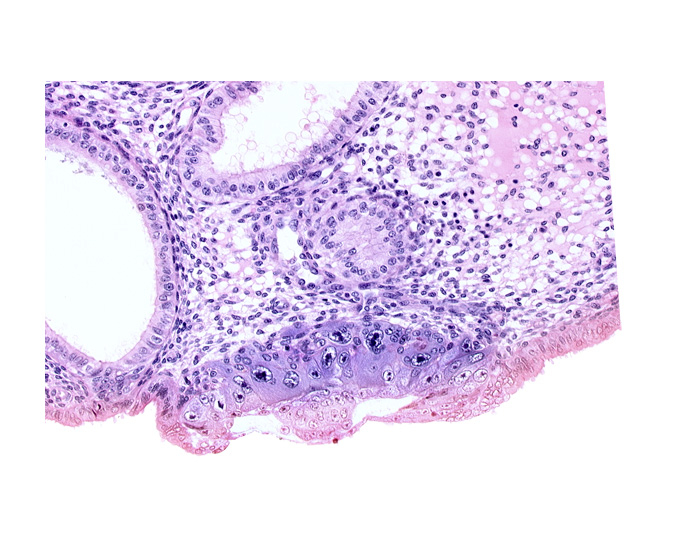

0 μm

Carnegie Embryo #8020 | Location: 06-02-05

Keywords: amnioblast(s), blastocystic cavity (blastocoele), cytotrophoblast, embryonic disc, endometrial sinusoid, lumen of endometrial gland, membranous trophoblast at abembryonic pole, solid syncytiotrophoblast, uterine cavity

Source: The Virtual Human Embryo.